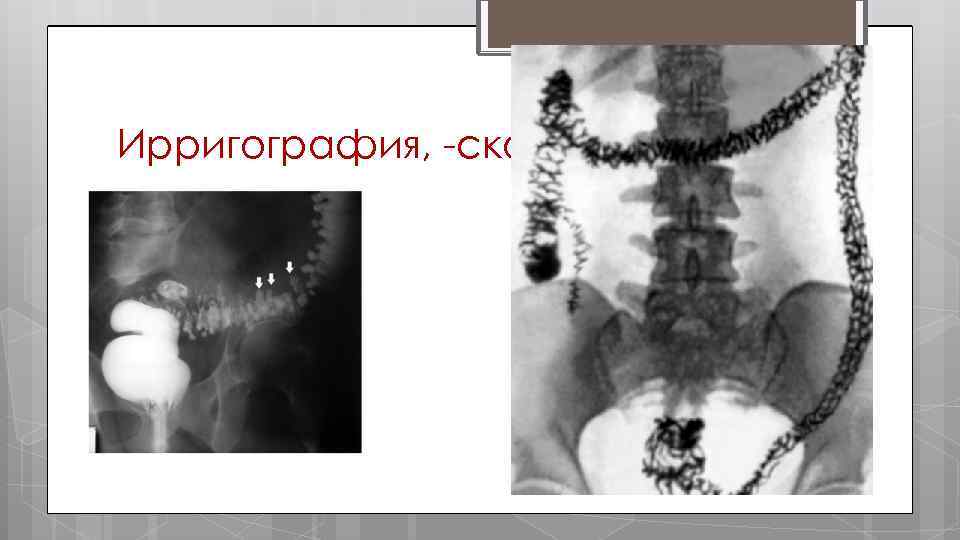

Диагностика дивертикулёза толстой кишки. Ирригография, скопия Колоноскопия Общий анализ крови Диагноз м. б. подтверждён с помощью: o КТ o УЗИ

Ирригография, скопия

ДИАГНОСТИЧЕСКАЯ ПРОГРАММА анамнез; объективное обследование; пальцевое исследование прямой кишки; ректороманоскопия; колоноскопия с прицельной биопсией; ультразвуковое обследование; рентгенологическое обследование ЖКТ с барием; ирригография; лабораторное обследование; бактериологическое обследование.

Неспеци фический язвенный колит, симптом "водосточ ной трубы". Ирригогр ама.

Неспеци фически й язвенный колит, симптом "водосточ ной трубы". Ирригогр ама.